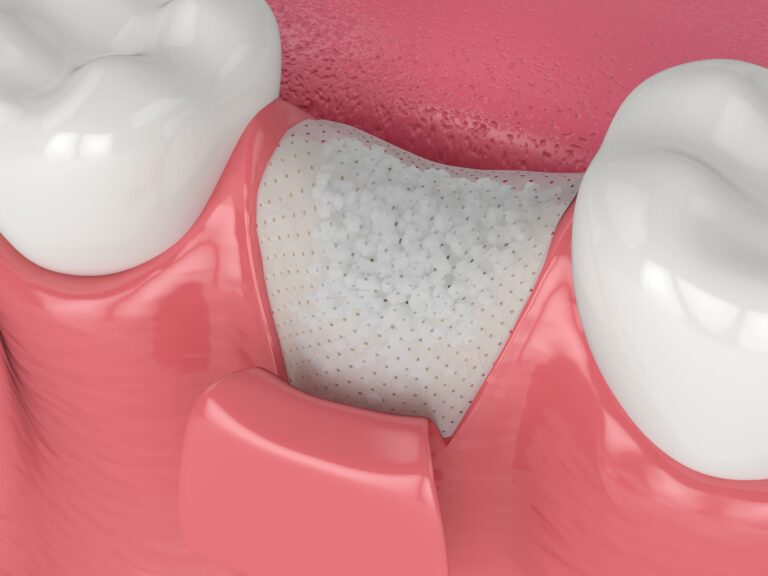

La gengivite e la parodontite sono malattie delle gengive e dei tessuti che circondano e supportano i denti e sono causate dai batteri contenuti nella placca e nel tartaro.